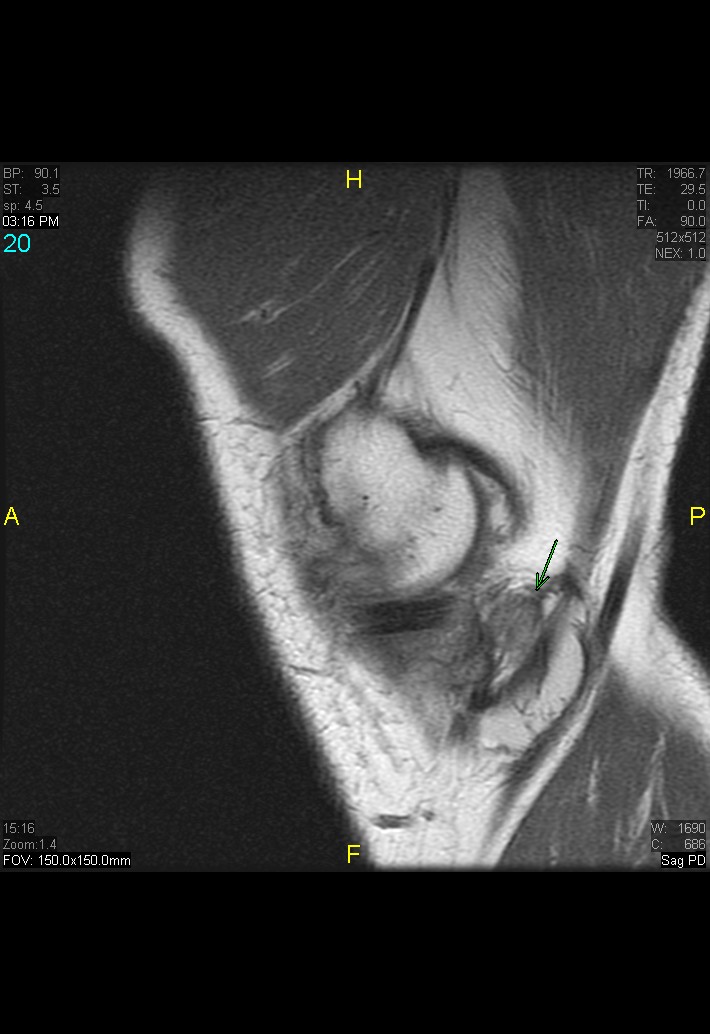

Figure 4 for case gout arthritis ( RID3567 )

Figure 4